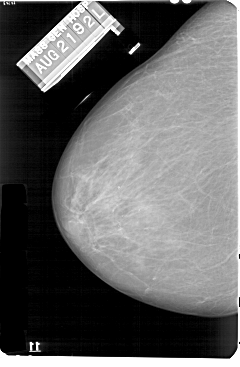

A_1131_1.LEFT_MLO

LEFT_MLO LINES 5491 PIXELS_PER_LINE 3766 BITS_PER_PIXEL 12 RESOLUTION 43.5 NON_OVERLAY